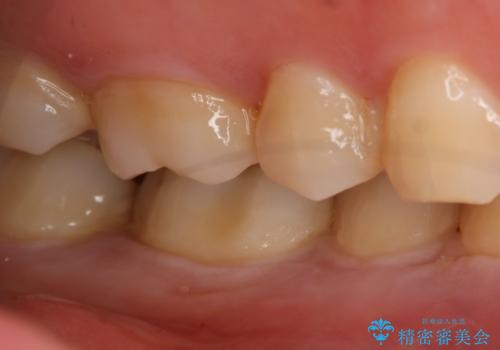

- 右下奥歯の虫歯治療を希望された患者様です。

保険の材料が劣化し、直下で虫歯の存在が確認出来ました。

セラミックを希望されたので形態・切削量を考慮し、セラミックインレーでの治療を計画しました。

虫歯が広く進行していましたが神経には到達していなかったので、予定通りセラミックインレーでの治療を行いました。